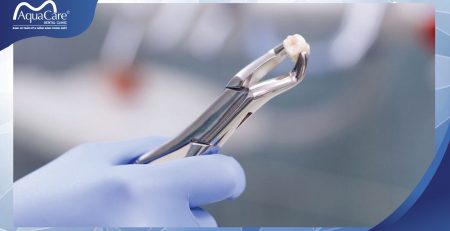

4. Nhổ răng khôn

Bác sĩ sẽ thực hiện thao tác tách nướu nhanh và vừa đủ chuẩn để làm lộ chân răng khôn, sau đó dùng mũi siêu âm cắt đứt dây chằng nha chu rồi lấy răng khôn ra khỏi xương hàm. Thường một ca nhổ răng khôn chỉ mất 15-20 phút và không hề có cảm giác đau đớn trong suốt quá trình nhổ. Sau khi răng khôn được lấy ra, bác sĩ sẽ cầm máu cho bạn và tiến hành khâu vết thương nếu cần. Máu sẽ ngưng chảy khoảng 10-20 phút sau đó.